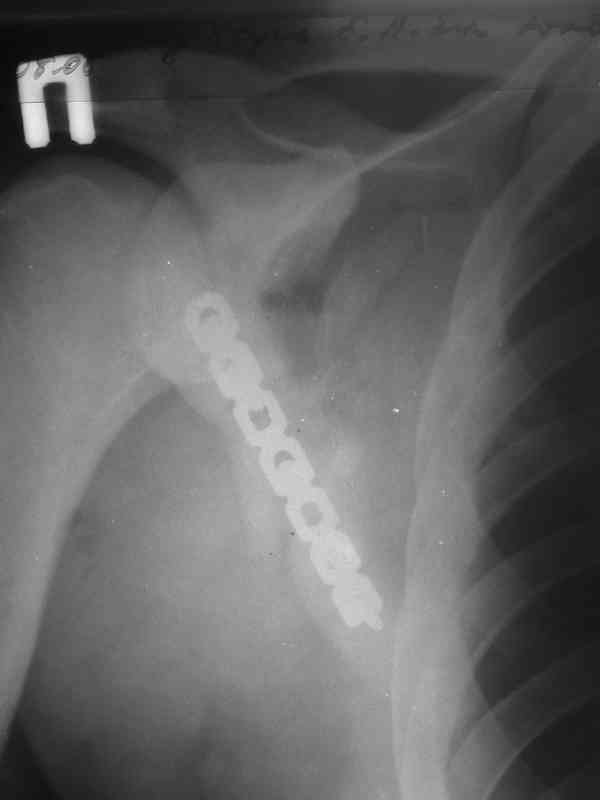

Уважаемые коллеги, помогите определиться с тактикой. Больной 1953гр, травма на стройке, придавило тяжелымпредметом. Сейчас в сознании, стабилен, плевральная полость задренирована. Предполагаем синтез ключицы, если бы не переломы ребер, установили бы шину ЦИТО.Есть у кого опыт открытого/закрытого синтеза подобной лопатки? Что делать с клювовидным отростком? Спасибо, Моисеев Ю.И.

2. Остеосинтез лопатки из заднего доступа(рекон.LCP, LC-LCP 3,5мм, Т-обр.LCP 3,5мм); ключицу стандартно